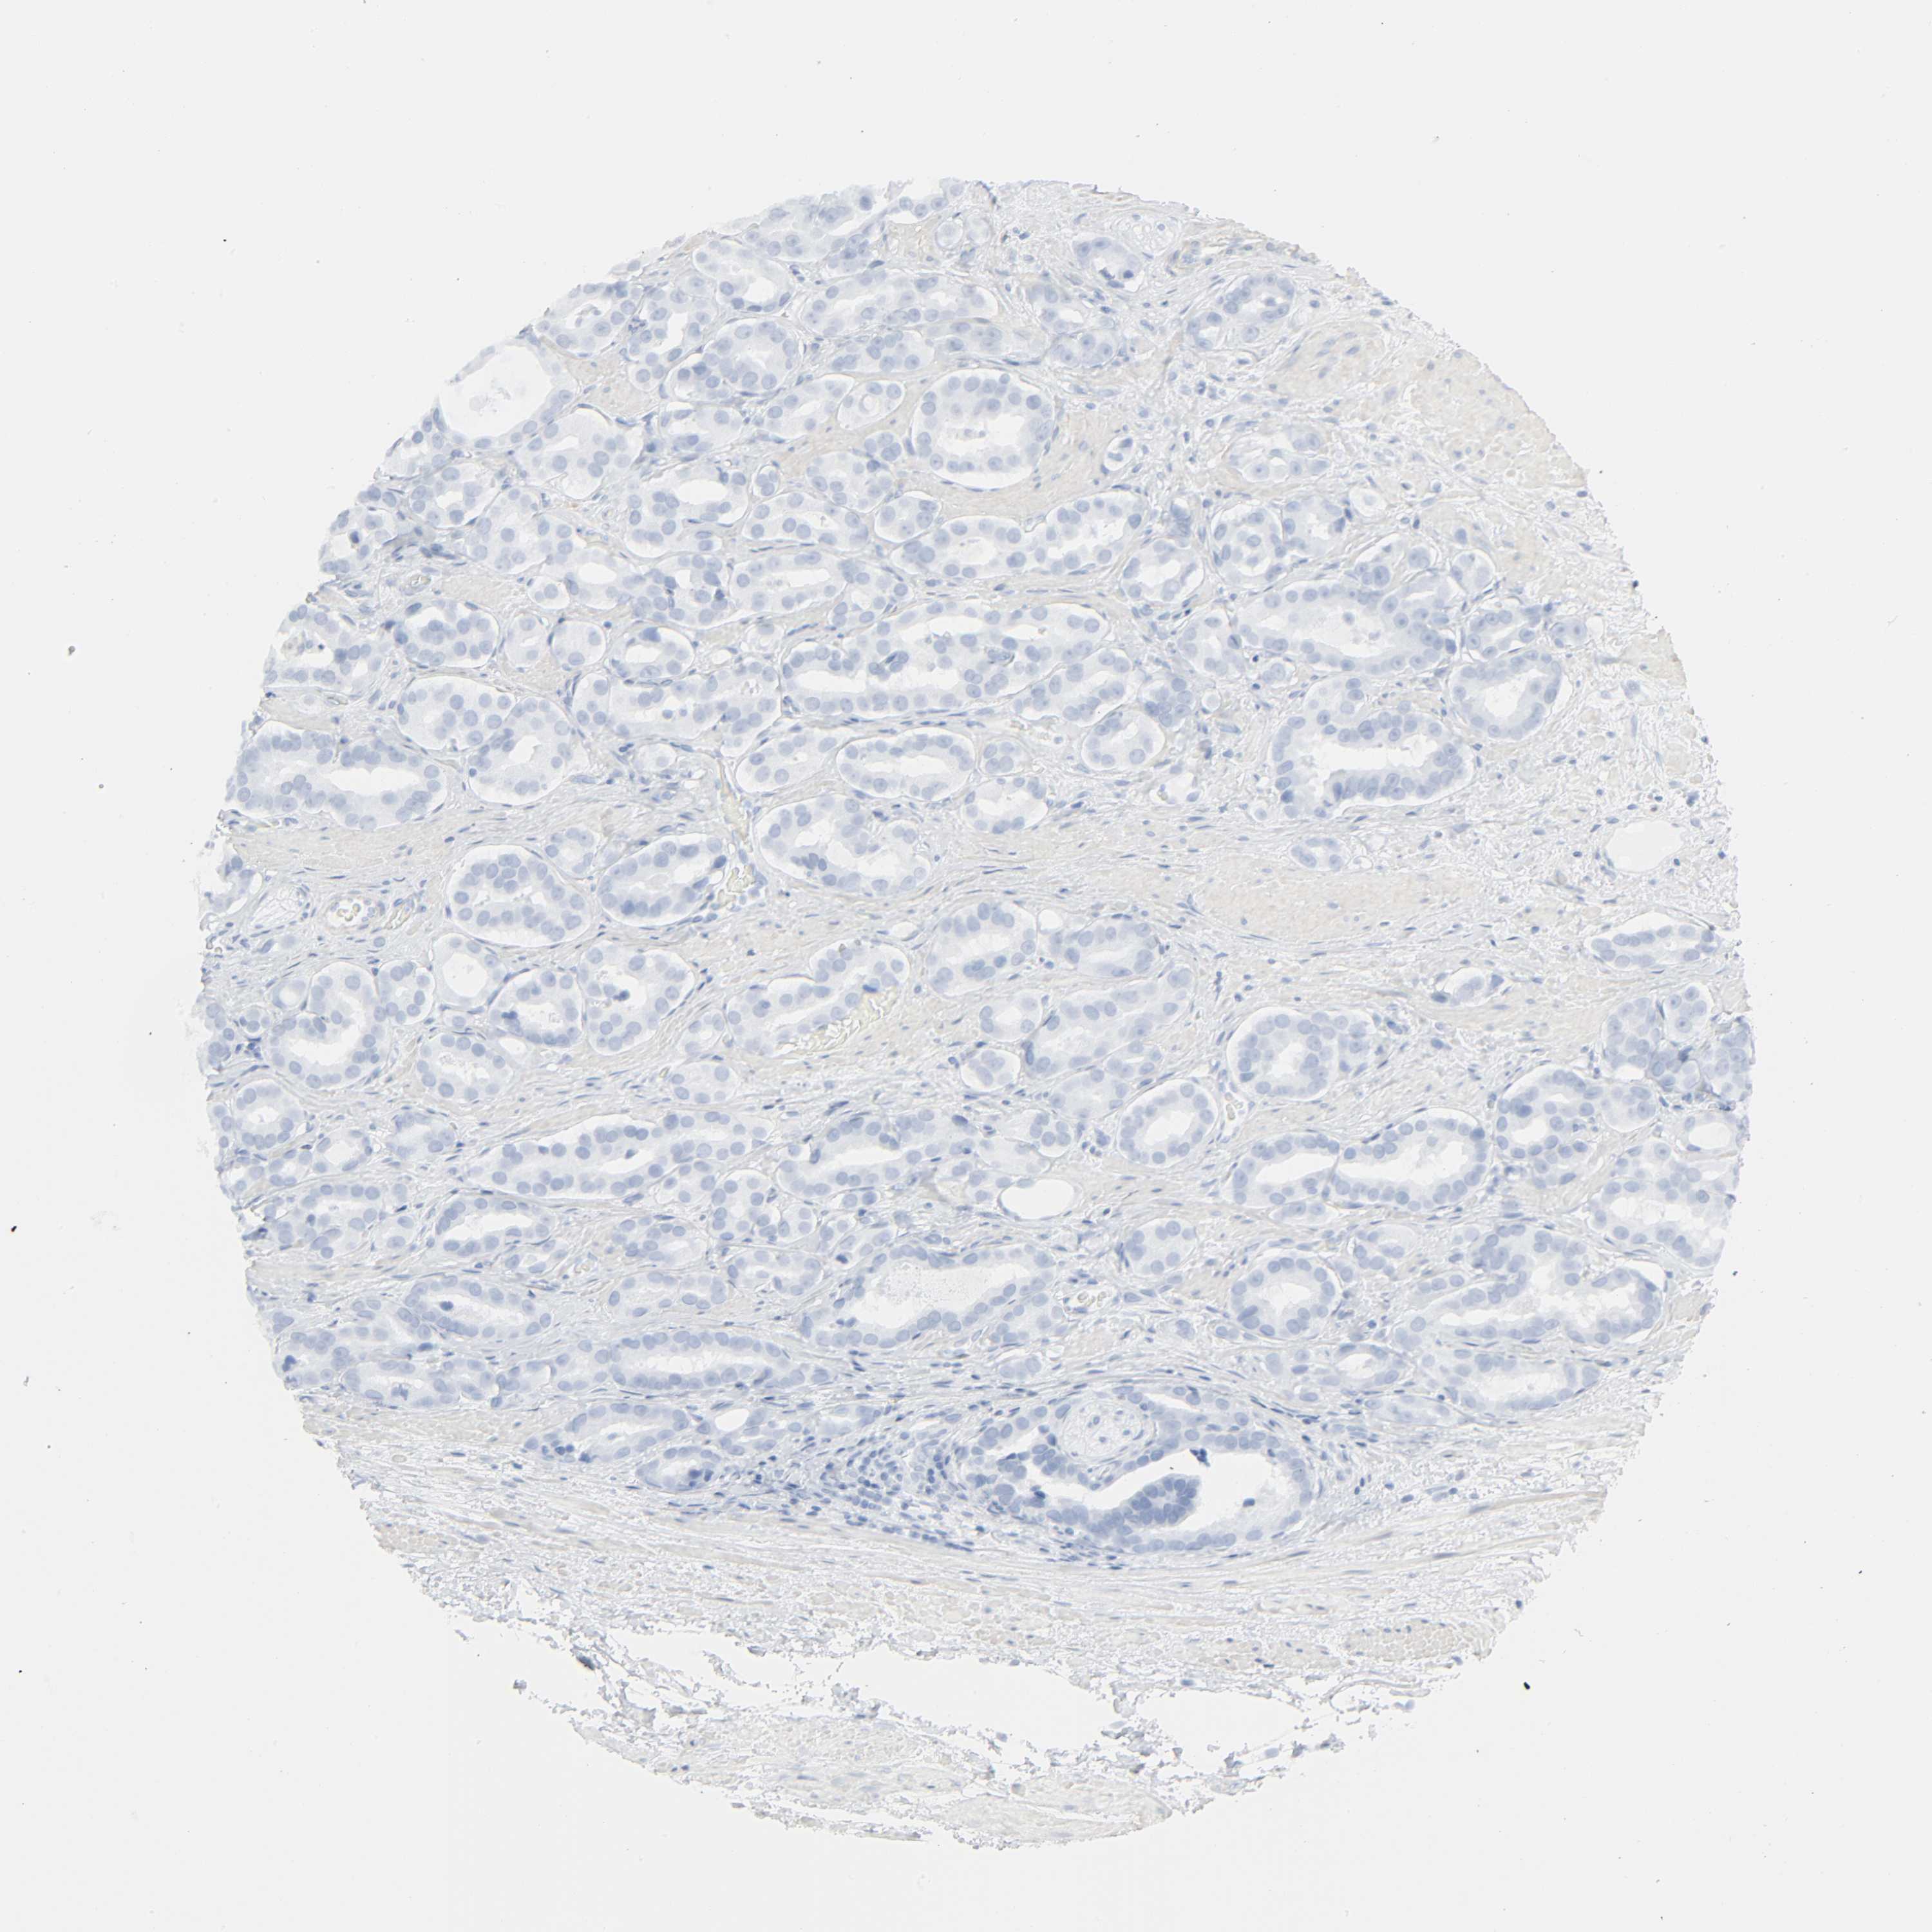

PROSTATE CANCER - Protein expressioni

A mouse-over function shows sample information and annotation data. Click on an image to view it in a full screen mode. Samples can be filtered based on level of antibody staining by selecting one or several of the following categories: high, medium, low and not detected. The assay and annotation is described here.

Note that samples used for immunohistochemistry by the Human Protein Atlas do not correspond to samples in the TCGA dataset.

Antibody stainingi

Antibody staining in the annotated cell types in the current human tissue is reported as not detected, low, medium, or high, based on conventional immunohistochemistry profiling in selected tissues. This score is based on the combination of the staining intensity and fraction of stained cells.

Each image is clickable and will lead to virtual microscopy that enables deeper exploration of all samples and also displays staining intensity scores, fraction scores and subcellular localization as well as patient and tissue information for each sample.

Antibody HPA001499

Antibody CAB004540

Staining

High

Medium

Low

Not detected

Intensity

Strong

Moderate

Weak

Negative

Quantity

>75%

75%-25%

<25%

None

Location

Nuclear

Cytoplasmic/membranous

Cytoplasmic/membranous,nuclear

Adenocarcinoma, Medium grade

Adenocarcinoma, High grade

Adenocarcinoma, Low grade